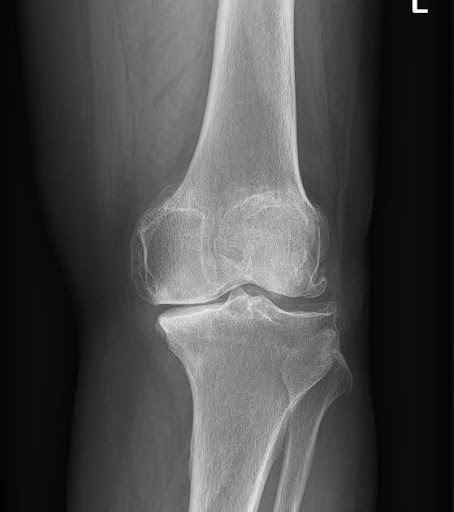

Knee osteoarthritis (OA) is a progressive condition where cartilage slowly breaks down, leading to stiffness, pain, and loss of mobility. The Kellgren-Lawrence (KL) grading system defines early OA as:

- Grade 1: Minimal joint changes, doubtful narrowing

- Grade 2: Definite narrowing with osteophytes

- Grade 3: Moderate narrowing, frequent pain and stiffness

At these stages, cartilage is still present—making regenerative therapies most effective.